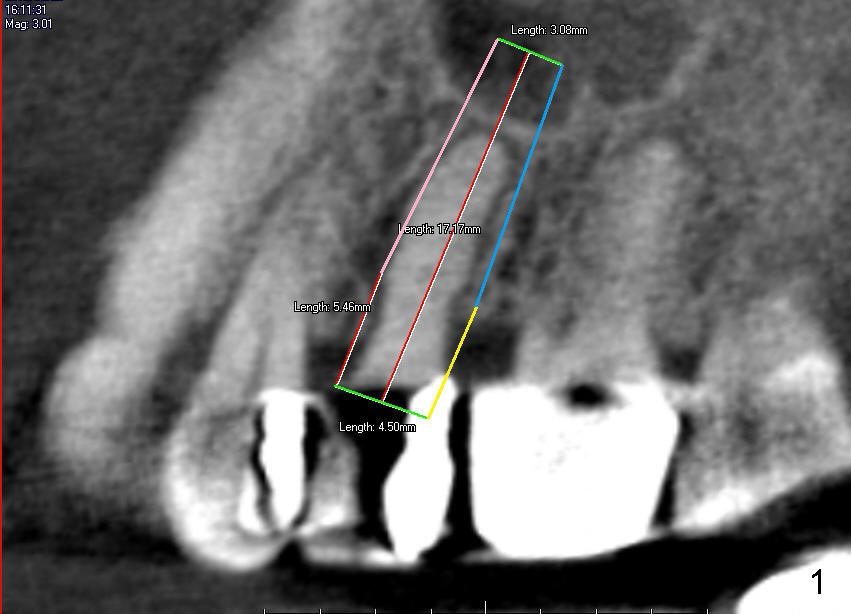

The tooth #13 has broken down to residual root now. CBCT sagittal (Fig.1,3) and coronal (Fig.2,4) sections show designs of T (4.5x17 mm Fig.1,2) and D2 (Fig.3,4) implants. Which is better? It appears that sinus lift with bone graft is expected.

In fact, D2 implant is placed.